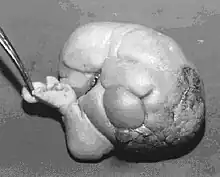

Fetus in fetu (or foetus in foetu) is a rare developmental abnormality in which a mass of tissue resembling a fetus forms inside the body of its twin. An early example of the phenomenon was described in 1808 by George William Young.[1]

Fetus in fetu may be a very highly differentiated form of dermoid cyst, itself a highly differentiated form of mature teratoma.[5]

Fetus in fetu may be a parasitic twin fetus growing within its host twin. Very early in a monozygotic twin pregnancy, in which both fetuses share a common placenta, one fetus wraps around and envelops the other. The enveloped twin becomes a parasite, in that its survival depends on the survival of the host twin, by drawing on the host twin's blood supply. The parasitic twin is anencephalic (without a brain) and lacks some internal organs, and as such is unable to survive on its own. As the host twin has to "feed" the enveloped twin from the nutrients received over a single umbilical cord, they usually die before birth.